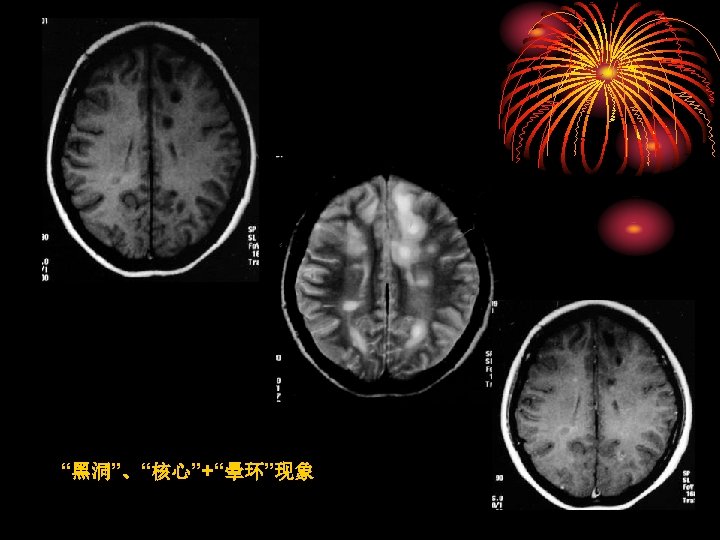

• TDLs非闭合性增强是鉴别诊断的依据之 一;非脱鞘病(炎症、肿瘤等)只有7%出 现非闭合性环形增强 • TDLs水肿程度及占位效应相对较轻 Distinguishing Tumefactive Demyelinating Lesions from Glioma or Central Nervous System Lymphoma: Added Value of Unenhanced CT Compared with Conventional Contrast-enhanced MR Imaging Radiology 2009, 251(2): 467 -484